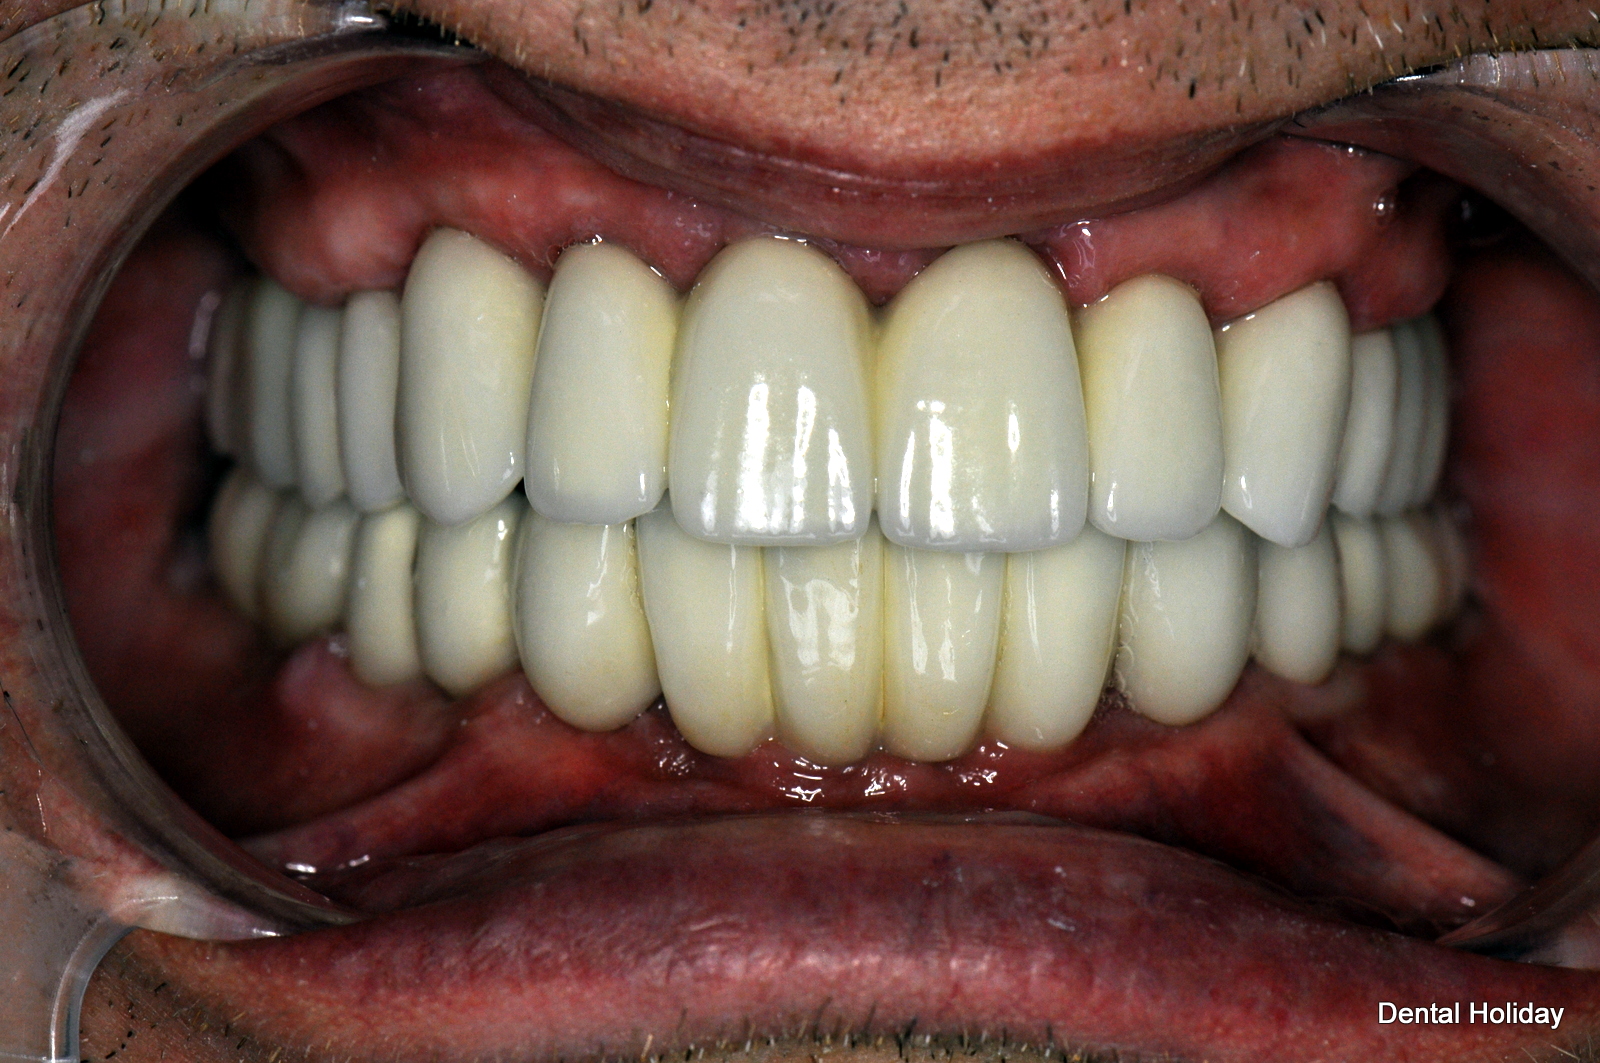

As you can see on the x-ray here, this included 14 implants and 28 crowns in total, as unfortunately most of his teeth were loose. As you can see from the photographs, the final results provided a fixed, balanced smile, with no worry of ever having to wear a dreaded denture.

Temporary teeth were fitted for him straight after the first dental implant treatment session, so that there was even no denture or toothless situation to face over the Christmas holidays, and he could munch happily on a full English roast dinner.

In the picture collage you can see the immediate change from loose unstable teeth to permanent fixed temporary bridges: